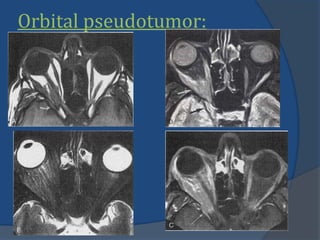

Orbital pseudotumor:

 MR imaging:

 Hypointense tonormal

muscle on TIWIs.

 Iso-intense to slighly

hyper-intense on

T2WIs and STIR.

 Due to high cellular

component and

fibrosis.

 Marked diffuse in-

homogenous

enhancement.

Orbital pseudotumor:  MRimaging:  Hypointense tonormal muscle on TIWIs.  Iso-intense to slighly hyper-intense on T2WIs and STIR.  Due to high cellular component and fibrosis.  Marked diffuse in- homogenous enhancement.